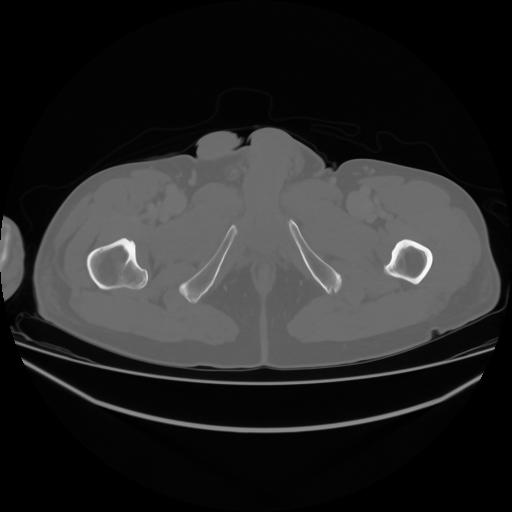

4 CUERPO,CE,Axial,3.0,CUERPO,,